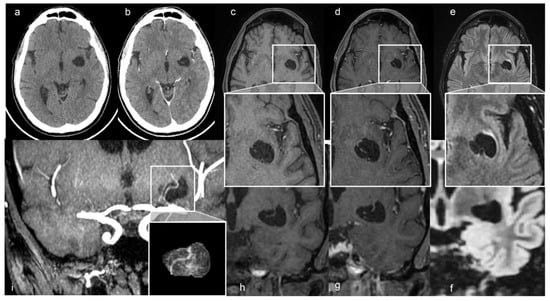

A 48-year-old man presented with a one-year history of diabetes mellitus (DM) type 1, diabetic polyuria, and polydipsia. Two months earlier, he had a fever (40 °C) for many days, partially resolved with broad-spectrum antibiotic therapy. One week later, he developed acute urinary retention. The abdominal ultrasound study showed up portal vein thrombosis and prostatic hypertrophy with calcifications. The Computed Tomography (CT) study of the abdomen showed a fluid/superfluid collection in the paramesocolic groove, extending caudally, reaching the recto-vesical cavity, where it appears partially organized. From the spleen-mesenteric confluence to the hepatic hilum, the vena porta was occluded until its lobar and segmentary branches suggesting thrombophlebitis. The liver was swollen, with irregular borders and inhomogeneous, for portal perfusion defects. The spleen appeared to increase in size (craniocaudal length: 150 mm) with an accessory spleen (about 12 mm) above the superior pole. Multiple confluent and increased-in-size pathologic abdomen-pelvic and liver hilum lymph nodes were seen. The abdominal aorta was diffusely atheromatic. Blood analysis revealed infection: C-reactive protein (CRP) 20 mg/dL, white blood cells (WBC) 15,000/mm3, and the most are neutrophils (10,700 mm3), ESR 119 mm/hr, and blood sugar level 335 mg/dL. An adjunctive blood test confirmed a bacterial infection (streptococcus constellatum) responsible for pelvic abscess. The neurological examination was normal. The CT brain study showed a left capsule-lenticular-striatal homogenously hypodense rounded area with moderate mass effect, without peripheral contrast enhancement. Within the cystic-like area, a linear enhancing structure appeared after iodate contrast medium injection, suggesting a vessel (Figure 1a,b).

Figure 1.

(a) Axial non-contrast and (b) enhanced CT scan shows a left cystic-like intraparenchymal area, hisodense to CSF, suggestive of a GTPVS; in (b) note linear enhancing feature inside the cyst. Axial T1, T1 with gadolinium and FLAIR MRI sequences, (c–e) and magnified views; coronal T1, T1 with gadolinium and FLAIR MRI sequences (f–h) of GTPVS. Note in (e) the thin T2 hyperintensity surrounding the GTPVS, responsible for mild compression of neighboring parenchyma. (i) Coronal maximum intensity projection (MiP) TOF arterial 3D surfaces reconstruction of the GTPVS.

The MRI study confirmed the up-mentioned CT features, showing a cystic-like parenchymal area 3 × 2.8 cm in diameter and 3.0 cm3 volume, isointense to the CSF in all sequences, partially surrounded by a close thin area of gliosis, no contrast enhancement, but with better evidence of the linear structure within the area, compressing the neighboring brain structures (Figure 1). The 3D CISS sequence showed the “ribbon-like” structure inside the cystic-like lesion that the fusion image (CISS + TOF) confirmed to be a perforating artery with a redundant course (Figure 2). DWI and apparent diffusion coefficient (ADC) maps showed no signal restriction (not shown). Based on radiological studies, the diagnosis suggested a GTPVS.

We also performed a 3D reconstruction based on the FSPGR T1 sequence [24,25], showing the tight mutual connection between the GTPVS and penetrating vessels crossing it (Figure 1).